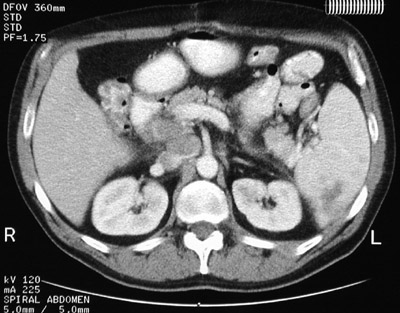

![]() | This abdominal CT scan reveals a larger and several smaller splenic mass lesions representing extranodal involvement by Hodgkin's disease. There is also prominent lymphadenopathy. In the view below from another patient, more prominent splenic involvement by Hodgkin's disease is seen. |